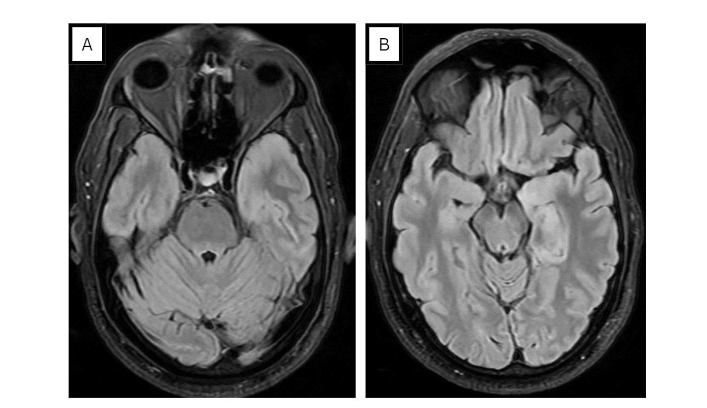

Laboratory investigations revealed neutrophilic leukocytosis in serum with a mildly elevated CRP. Bacterial cultures were negative, and both the chest X-ray (CXR) and CT head were unremarkable. However, an MRI of the brain showed T2/FLAIR hyperintensity in the left mesial temporal and temporal pole, associated with gyral edema (see Figure 1). There was with no post-contrast enhancement. Polymerase chain reaction (PCR) of cerebrospinal fluid (CSF) showed HSV-1 DNA, establishing the diagnosis of herpesvirus encephalitis and the patient was immediately started on acyclovir. Due episodic deterioration in the level of consciousness, levetiracetam 500mg BID was initiated. Subsequent EEG findings showed sub-continuous periodic lateralized discharges (PLDs) over the left hemisphere, along with bilateral independent periodic discharges (BIPDs) (see Figure 2).